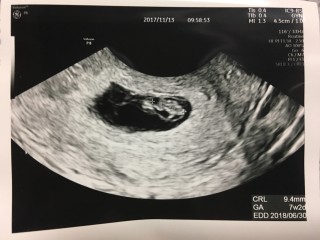

顕微鏡授精にて授かりました。一度の流産を経験していますが、7wでは心拍64程しかなく、CRLも6ミリ程でした。今回は心拍数含め順調とのことです。CRL9.4ミリ。母子手帳持参しましたが、次回の検診から補助券適用のようです。産婦人科は初診で6000円でした。やはり9wを越えないと一般的には不安ですが、今回のこの子は何故か信じられます。穏やかな気持ちでいます。出血も鮮血が1回、茶おりはほぼ毎日ありますが、先生からこの時期の出血は多いので気にしないように言われたので、気にせず前向きに過ごします。